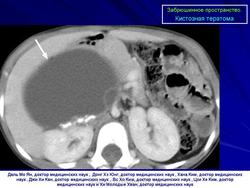

Забрюшинное пространство. Патология.